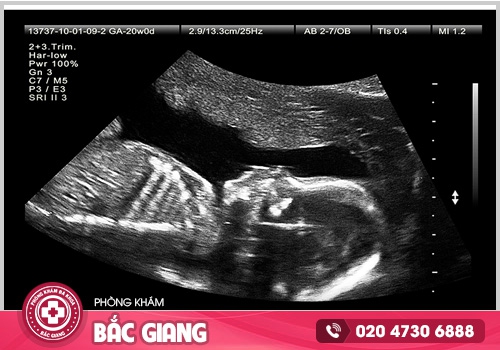

► Siêu âm 2D : Hình thức siêu âm cơ bản có giá tiền thấp nhất, phù hợp với nhu cầu siêu âm xem có thai hay không, xác định thai bao nhiêu phôi, kiểm tra vị trí thai nằm trong tử cung hay ngoài tử cung và phát hiện dị tật bẩm sinh nếu có.

► Máy siêu âm 4D: Máy siêu âm 4D hiện đại, cho hình ảnh rõ nét. Đây là kỹ thuật được tích hợp nhiều công nghệ thông minh, công cụ đắc lực giúp các bác sĩ chuyên khoa dễ dàng hơn trong việc quan sát và chẩn đoán, cũng như theo dõi quá trình phát triển của thai nhi.